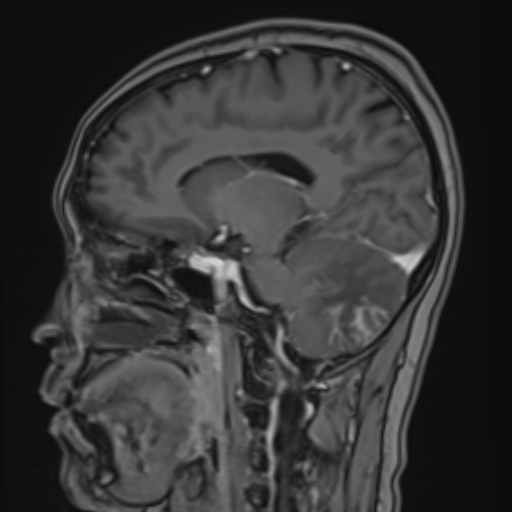

Enhanced myometrial vascularity is not a uterine AVM. This review clarifies definitions, key Doppler/MRI findings & management to avoid unnecessary embolization, hysterectomy & complications in post pregnancy bleeding. @StanfordBodyRad @stanfordRad bit.ly/463EX7M